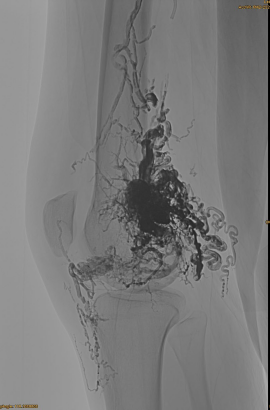

Grundlegende Informationen der Patienten: weiblich, 36 Jahre; AVM -Becken, Hip, Knie, linke OSG, mehrere Pre - Embolierungen.

Verwendete Produkte: 3pcs lava-34,14pcs lava-18.

Anfängliche DSA:

Endergebnis:

Kaum ein venöser Abfluss:

Spätphase, ein weiterer EMBO, der notwendig, aber viel besser ist: